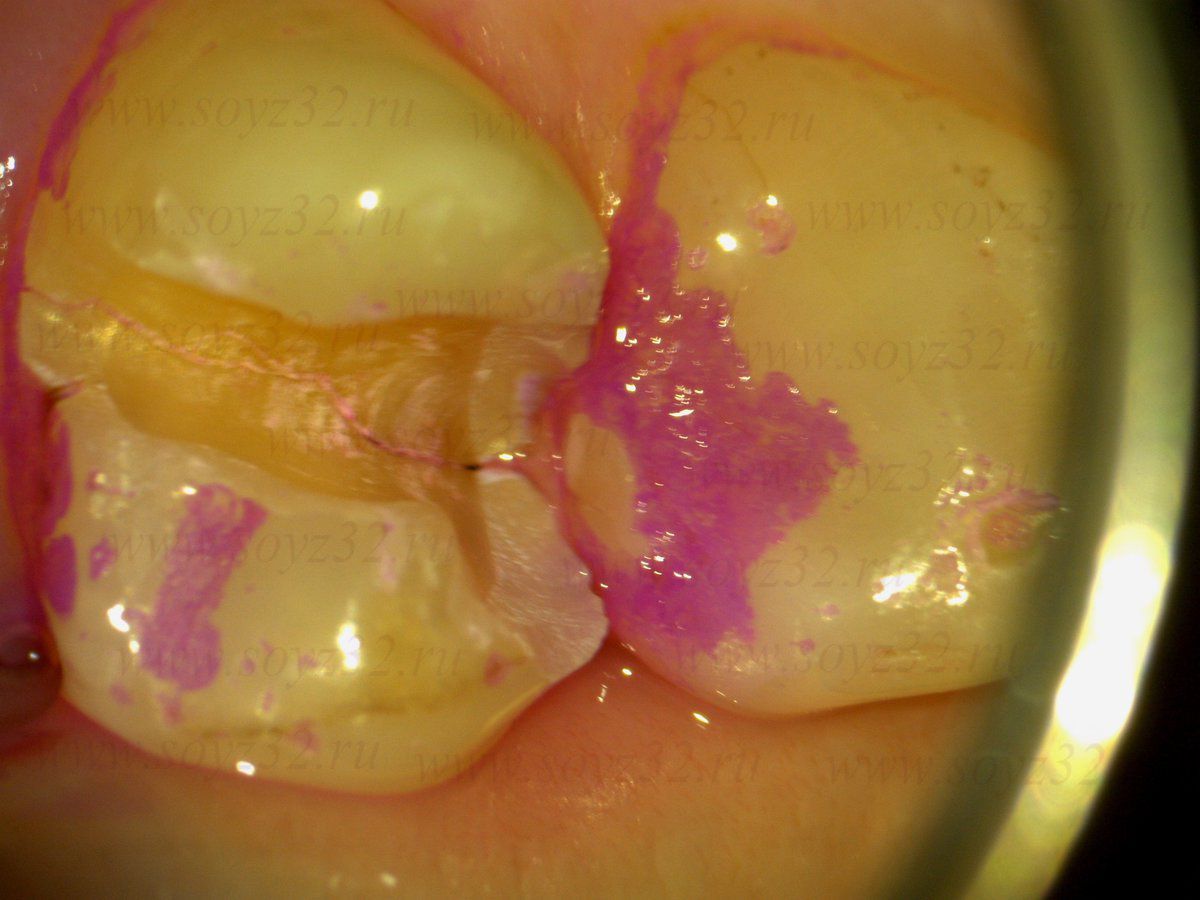

- Лечение кариеса

- Пломбирование

- Лечение зубов

По характеристикам наша стоматологическая клиника соответствует уровню ведущих европейских и американских клиник, с которыми врачи нашей стоматологии и зубные техники осуществляют обмен опытом. Это позволяет нам применять на практике только проверенные и хорошо зарекомендовавшие себя технологии и методики в лечении и протезировании зубов.